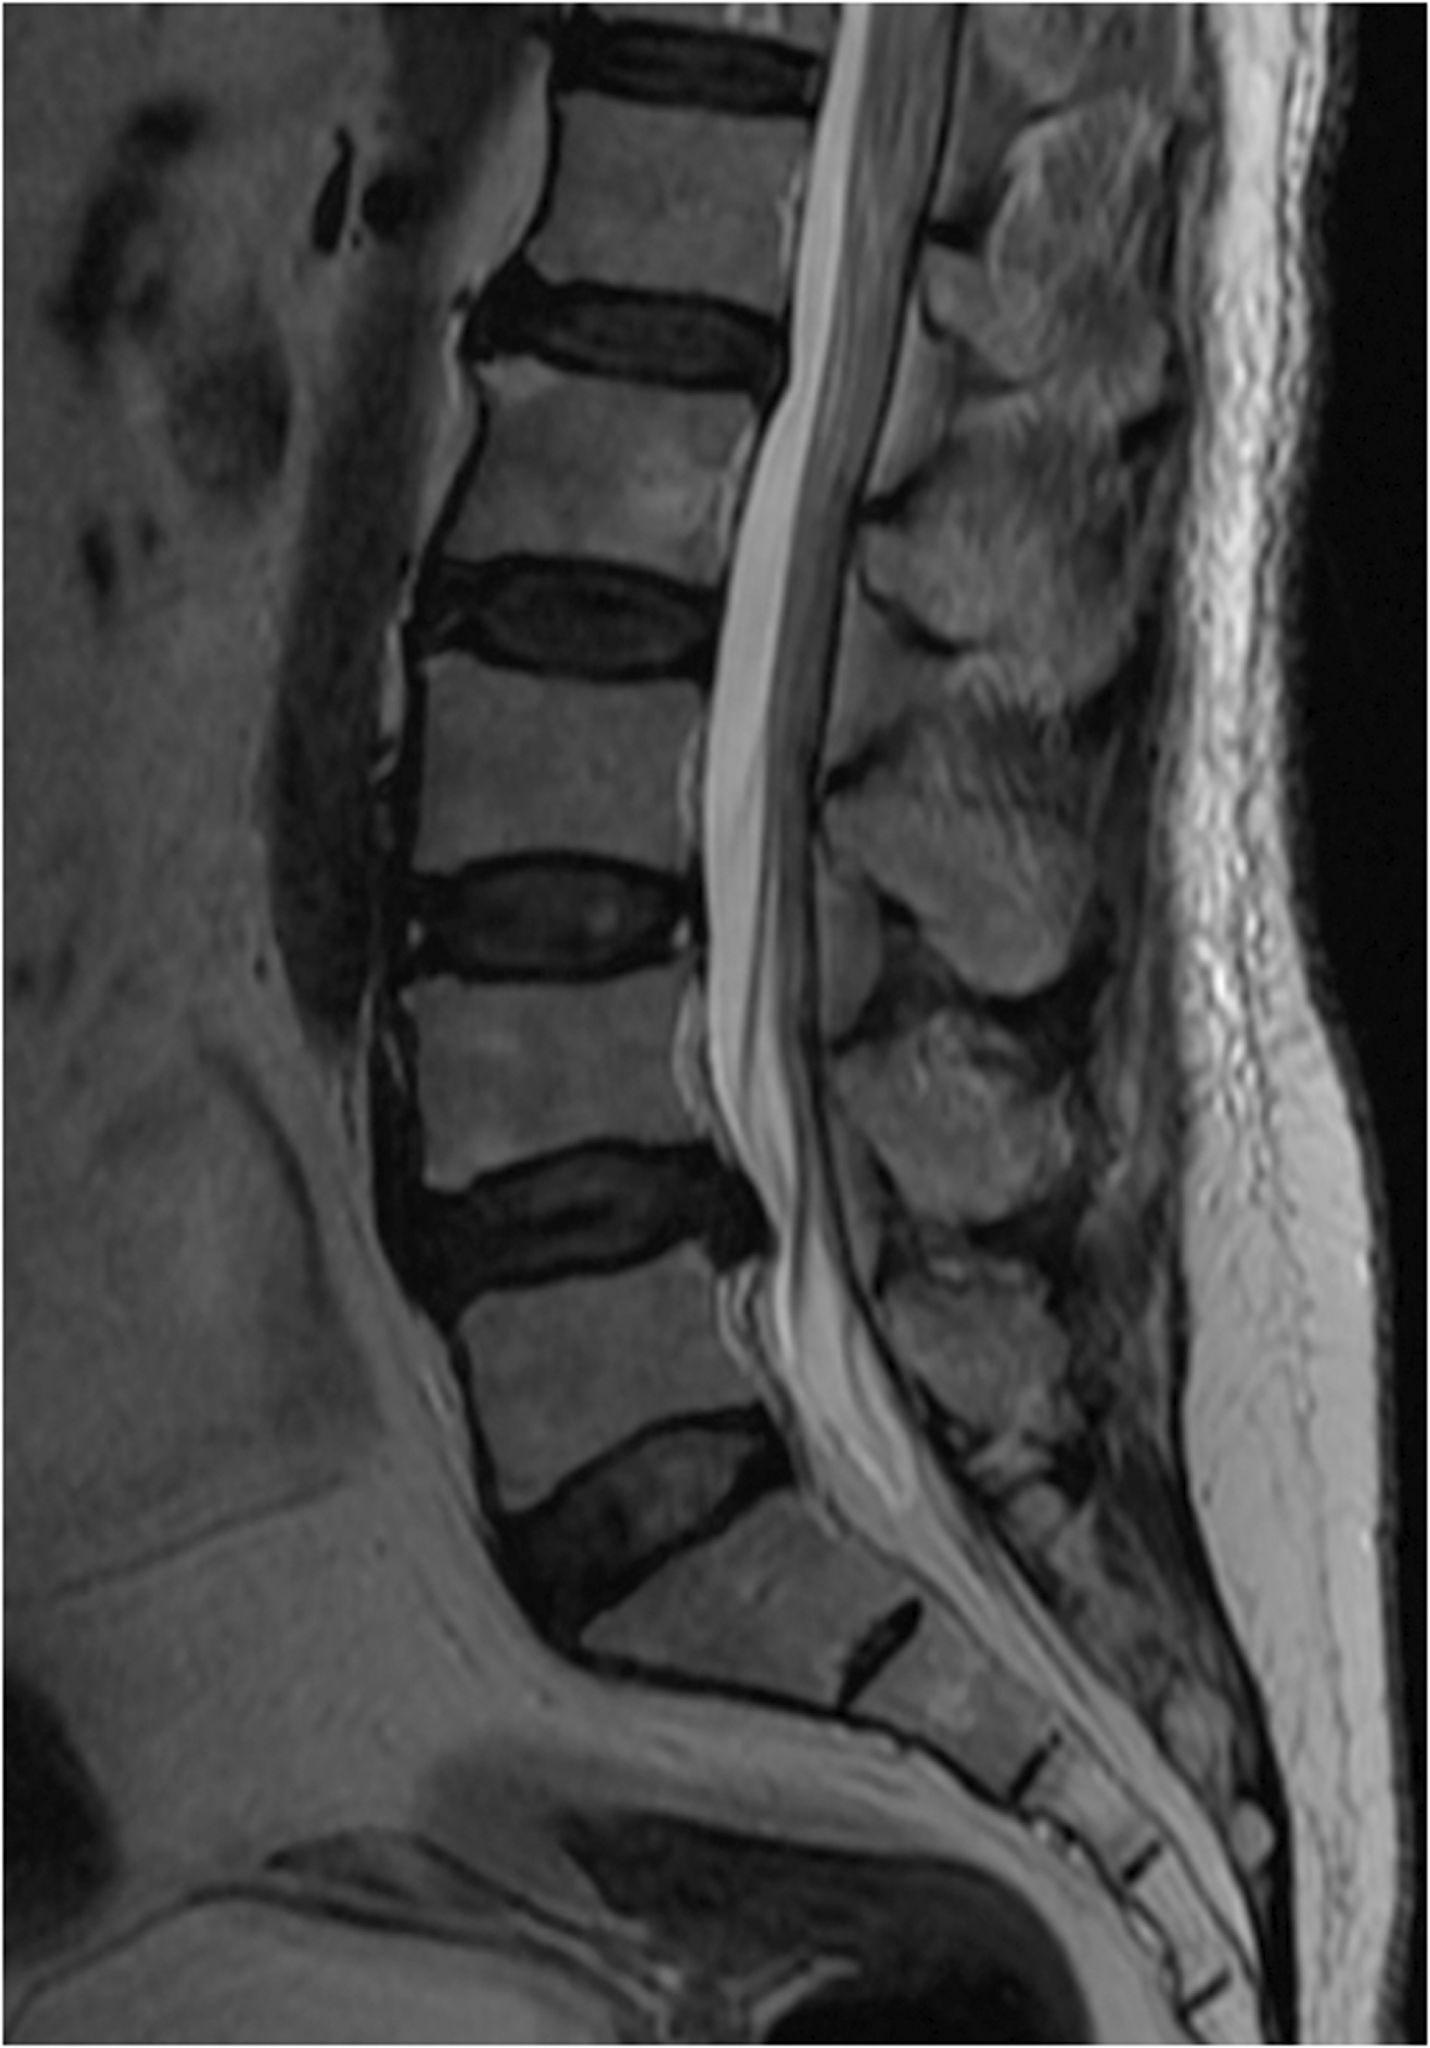

The spine is made of vertebrae, intervertebral discs, facet joints, ligaments, and nerves. Discs act as shock absorbers, while facet joints guide movement. When discs lose hydration or joints become overloaded, degenerative conditions begin to develop.

A herniated disc occurs when the inner disc material pushes through a tear in the outer disc wall. This can place pressure on spinal nerves and cause severe symptoms.

A bulging disc is an early form of disc degeneration where the disc extends outward but has not ruptured. Although often considered “less serious,” bulging discs can still irritate nerves and restrict movement.

Degenerative Disc Disease (DDD or DJD) occurs as discs lose hydration, elasticity, and height over time. This increases spinal instability and joint stress.